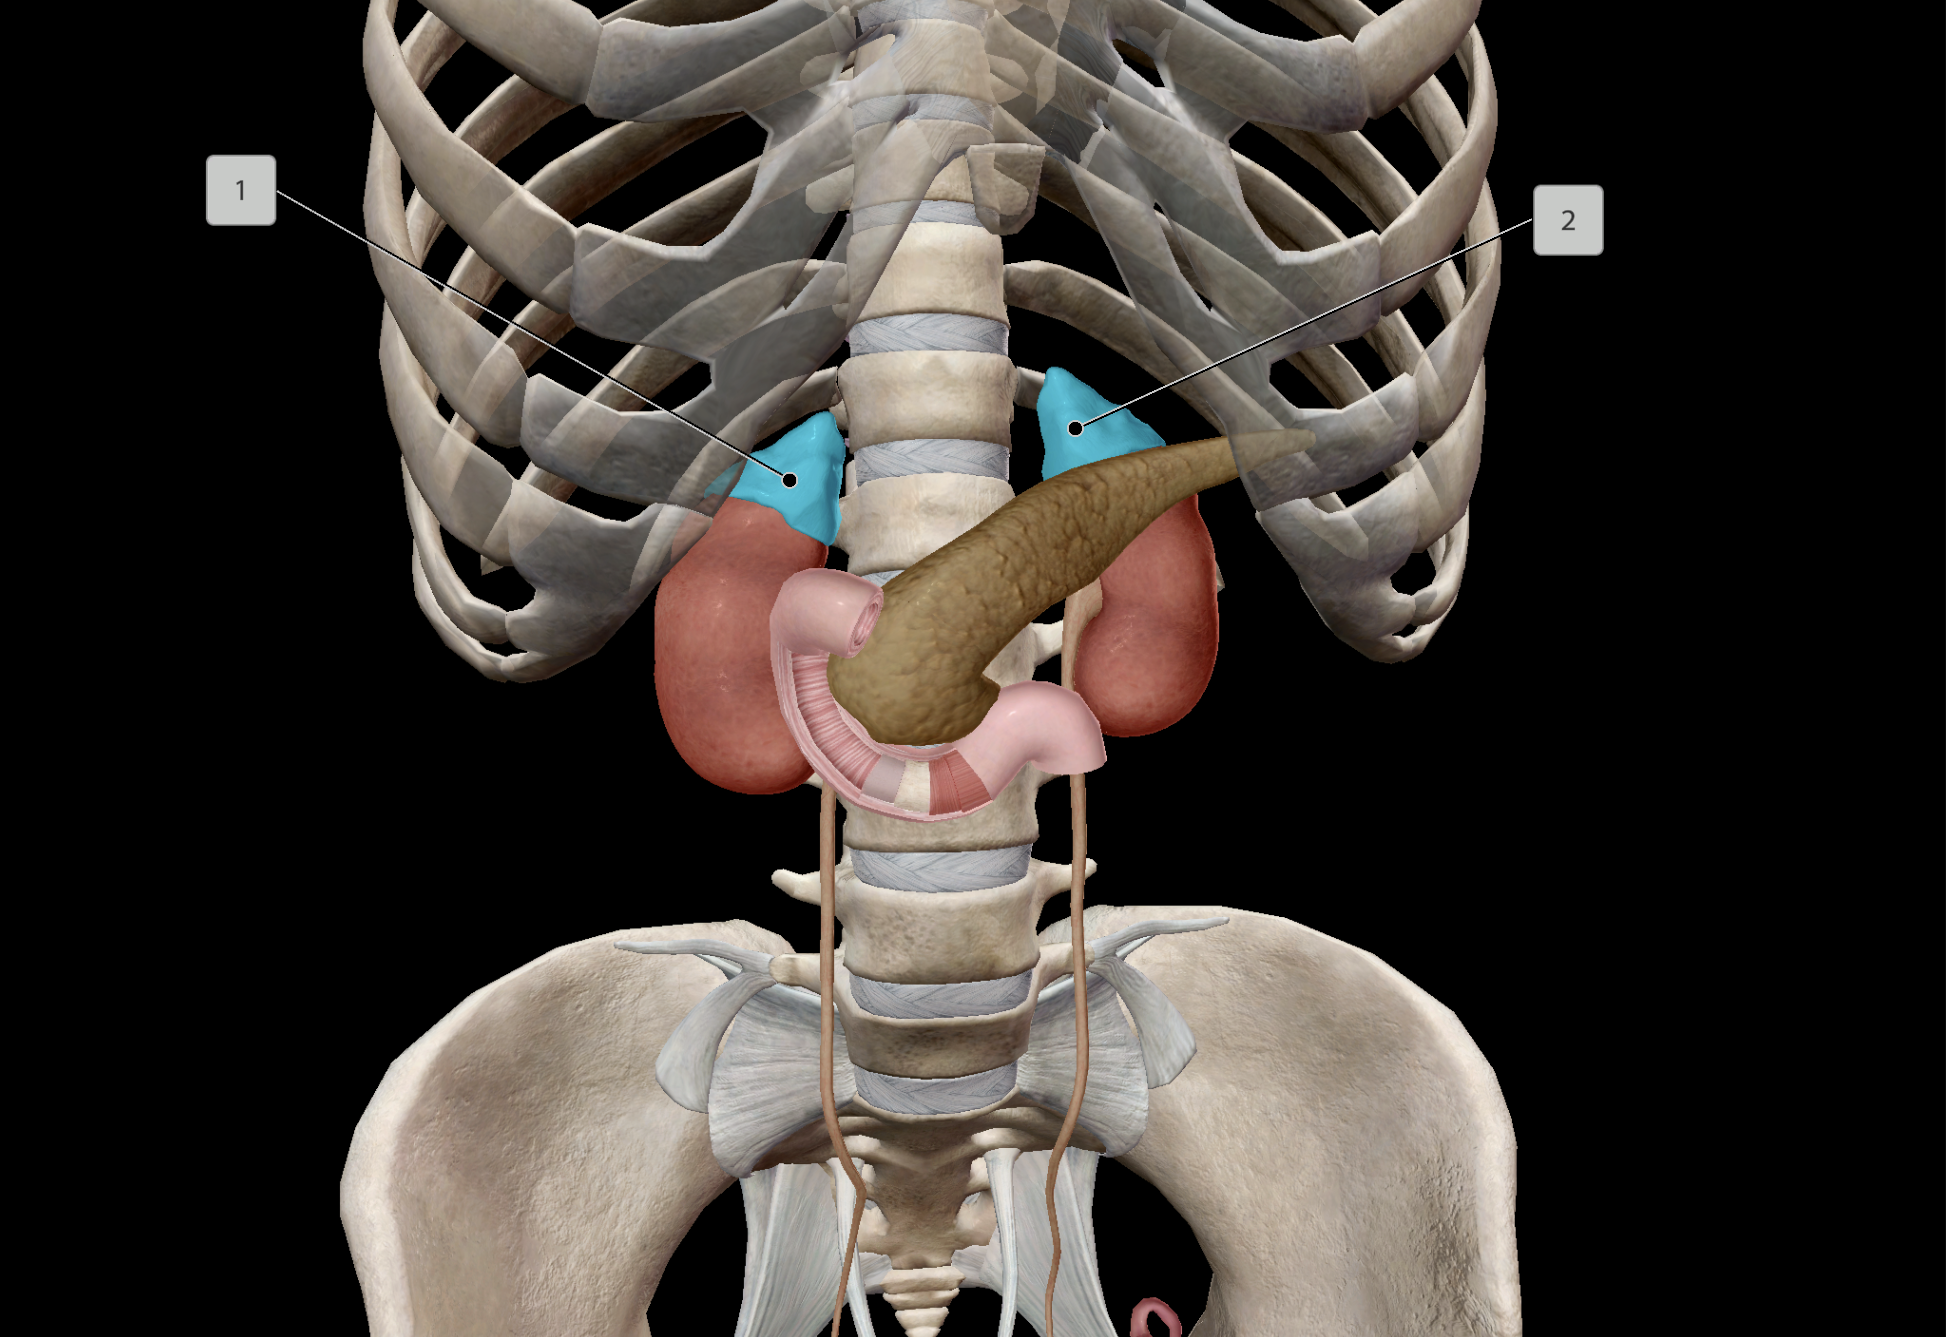

Adrenal Glands

Renal Artery